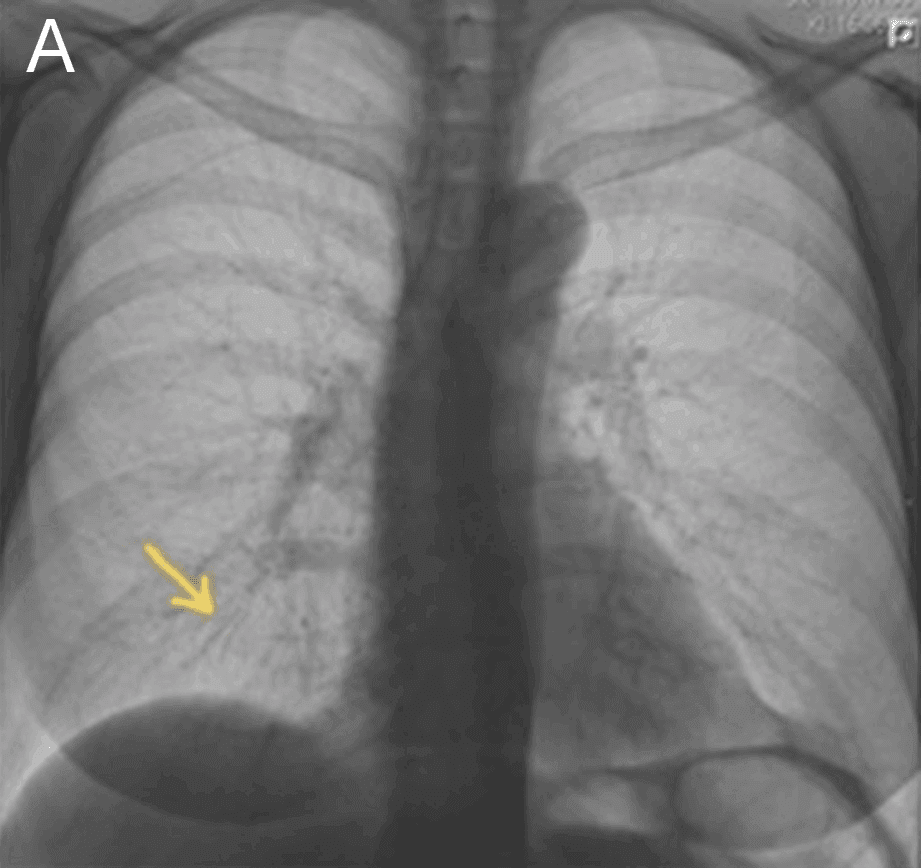

En 57-årig kvinde med cancer mammae sinister uden metastasering i forløb med neoadjuverende kemoterapi blev indlagt i akutmodtagelsen, da hun under MR-skanning udviklede varmefornemmelse og smerter i højre side af brystet. Skanningen blev afbrudt akut, og symptomerne forsvandt. Objektiv undersøgelse og blodprøver gav ingen afklaring. Røntgenundersøgelse af thorax viste et 18 mm langt fremmedlegeme i højre mellemlap (A). CT bekræftede et hyperdenst fremmedlegeme (B), mest sandsynligt i en subsegmental gren af a. pulmonalis til højre lunges mellemlap.

Måneden forinden havde patienten fået foretaget tilsvarende MR-skanning uden komplikationer. I mellemtiden havde hun ikke været udsat for et traume eller fået foretaget invasive undersøgelser fraset anlæggelse af perifert indsat centralt venekateter (PICC)-line. Den primære mistanke var derfor, at guidewire var knækket under anlæggelse. Der blev konfereret med vagthavende thoraxkirurg og interventionsradiolog, som vurderede, at fremmedlegemet grundet sin beliggenhed, størrelse samt fravær af symptomer var uden klinisk betydning.